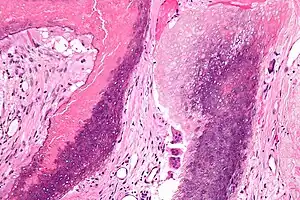

Micrograph of a pilomatricoma showing the characteristic "ghost" cells (anucleate squamous cells), benign viable squamous cells and multi-nucleated giant cells. H&E stain.

Pilomatricomas consist of anucleate squamous cells (called "ghost cells"), benign viable squamous cells and foreign body giant cells. These neoplasms have a characteristic transition of cells. The lining of the cyst consists of basoloid cells with indistinct cell borders and basophilic nuclei that mature into the eosinophilic anucleated squamous cells. The presence of calcifications with foreign body giant cells is common within the tumors.[13]